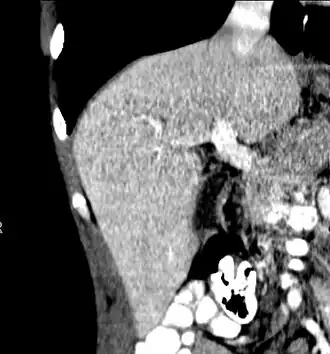

The diagnosis of liver disease is made by liver function tests, groups of blood tests, that can readily show the extent of liver damage. If infection is suspected, then other serological tests will be carried out. A physical examination of the liver can only reveal its size and any tenderness, and some form of imaging such as an ultrasound or CT scan may also be needed.

A CT scan in which the liver and portal vein are shown

With the recent advances of noninvasive imaging, living liver donors usually have to undergo imaging examinations for liver anatomy to decide if the anatomy is feasible for donation. The evaluation is usually performed by multidetector row computed tomography (MDCT) and magnetic resonance imaging (MRI). MDCT is good in vascular anatomy and volumetry. MRI is used for biliary tree anatomy. Donors with very unusual vascular anatomy, which makes them unsuitable for donation, could be screened out to avoid unnecessary operations.